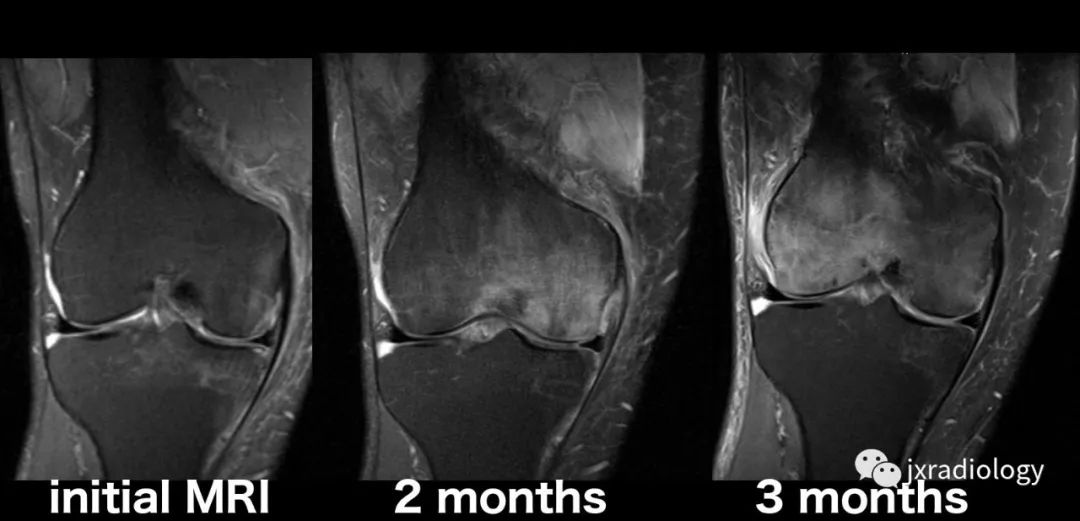

踝关节扭伤三个月,距骨坏死,术后两个月恢复 (原创)_损伤

膝关节磁共振最常见的骨质病变之骨髓水肿其病理原因及磁共振表现都在

收藏膝关节骨髓水肿影像综述